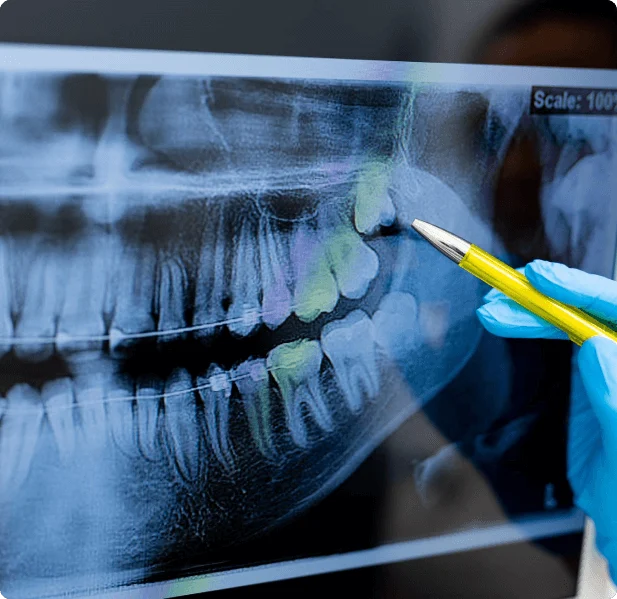

Wisdom teeth are typically removed in the late teens or early twenties because there is a greater chance that the teeth’s roots have not fully formed and the bone surrounding the teeth is less dense. These two factors can make extraction easier, as well as making the recovery time much shorter.

To remove a wisdom tooth, our doctors first needs to numb the area around the tooth with a local anesthetic. He can use additional medication to safely sedate you during the extraction if you are feeling nervous about the procedure. Since the impacted tooth may still be under the gums and imbedded in your jaw bone, our doctors will need to remove a portion of the covering bone to extract the tooth. To minimize the amount of bone that is removed with the tooth, he will often “section” your wisdom tooth so that each piece can be removed through a small opening in the bone. Wisdom tooth surgery typically takes less than an hour and patients can usually resume their normal activities within a few days.